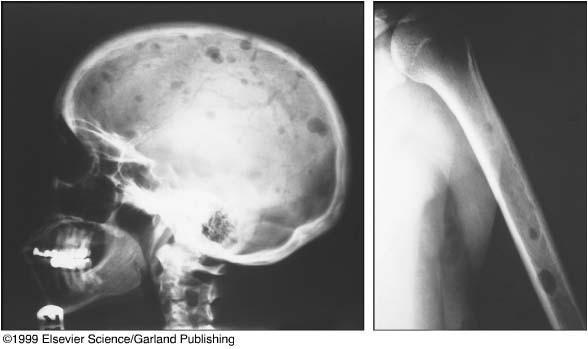

Bone Disease in Multiple Myeloma

Kyle RA. Mayo Clin Proc. 1975;50:29.

• A burdensome and frequent complication in MM

• Present in up to 80% of patients at diagnosis

• Characterized by osteolytic bone lesions secondary to increased bone resorption and impaired bone formation

• Sequelae

• Pathological fractures

• Osteoporosis

• Hypercalcemia

• Bone pain

• Spinal cord compression

Skeletal CT scan

K. Treiti et al. Skeletal Radiology 2021